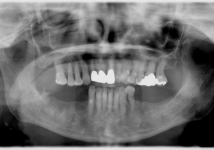

<症例2>60歳代 男性

長年放置したために歯周病が進行し噛みにくくなった患者様が、インプラントを入れ全顎的な治療を行い、審美改善しました。

レントゲン写真